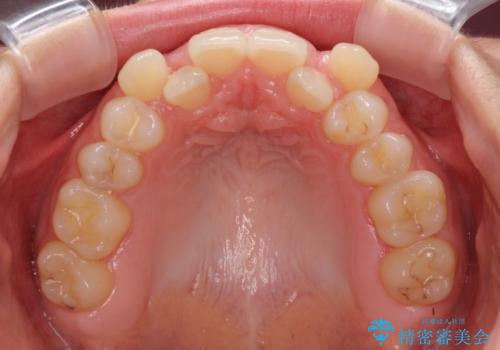

- 前歯のデコボコと八重歯を気にして来院された患者様です。

目立たない装置を希望されたので、上顎が裏側装置のハーフリンガルを選択し、左右上顎小臼歯1本ずつを抜歯して、矯正治療を行うこととしました。